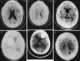

Hemiparesis, or unilateral paresis, is weakness of one entire side of the body (hemi- means "half"). Hemiplegia is, in its most severe form, complete paralysis of half of the body. [Source: Wikipedia ]